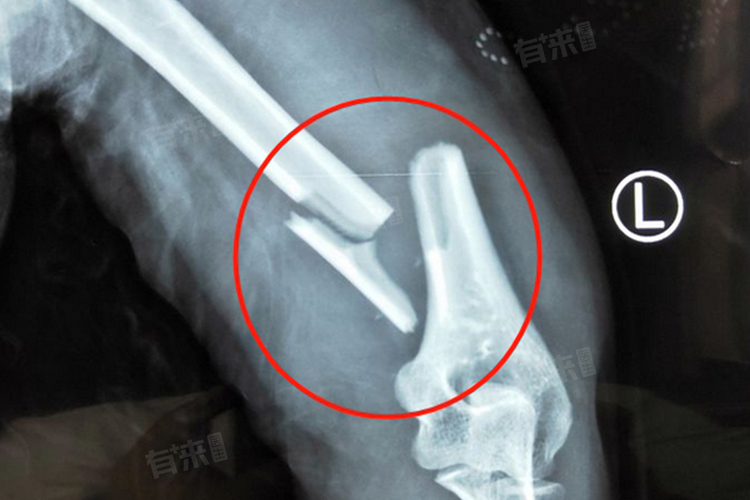

跟骨粉碎性骨折后,正常走路时间跨度较大,约3-9个月不等,受治疗方式、个人体质与康复训练状况等因素影响,各种因素对恢复进程都有影响的作用。